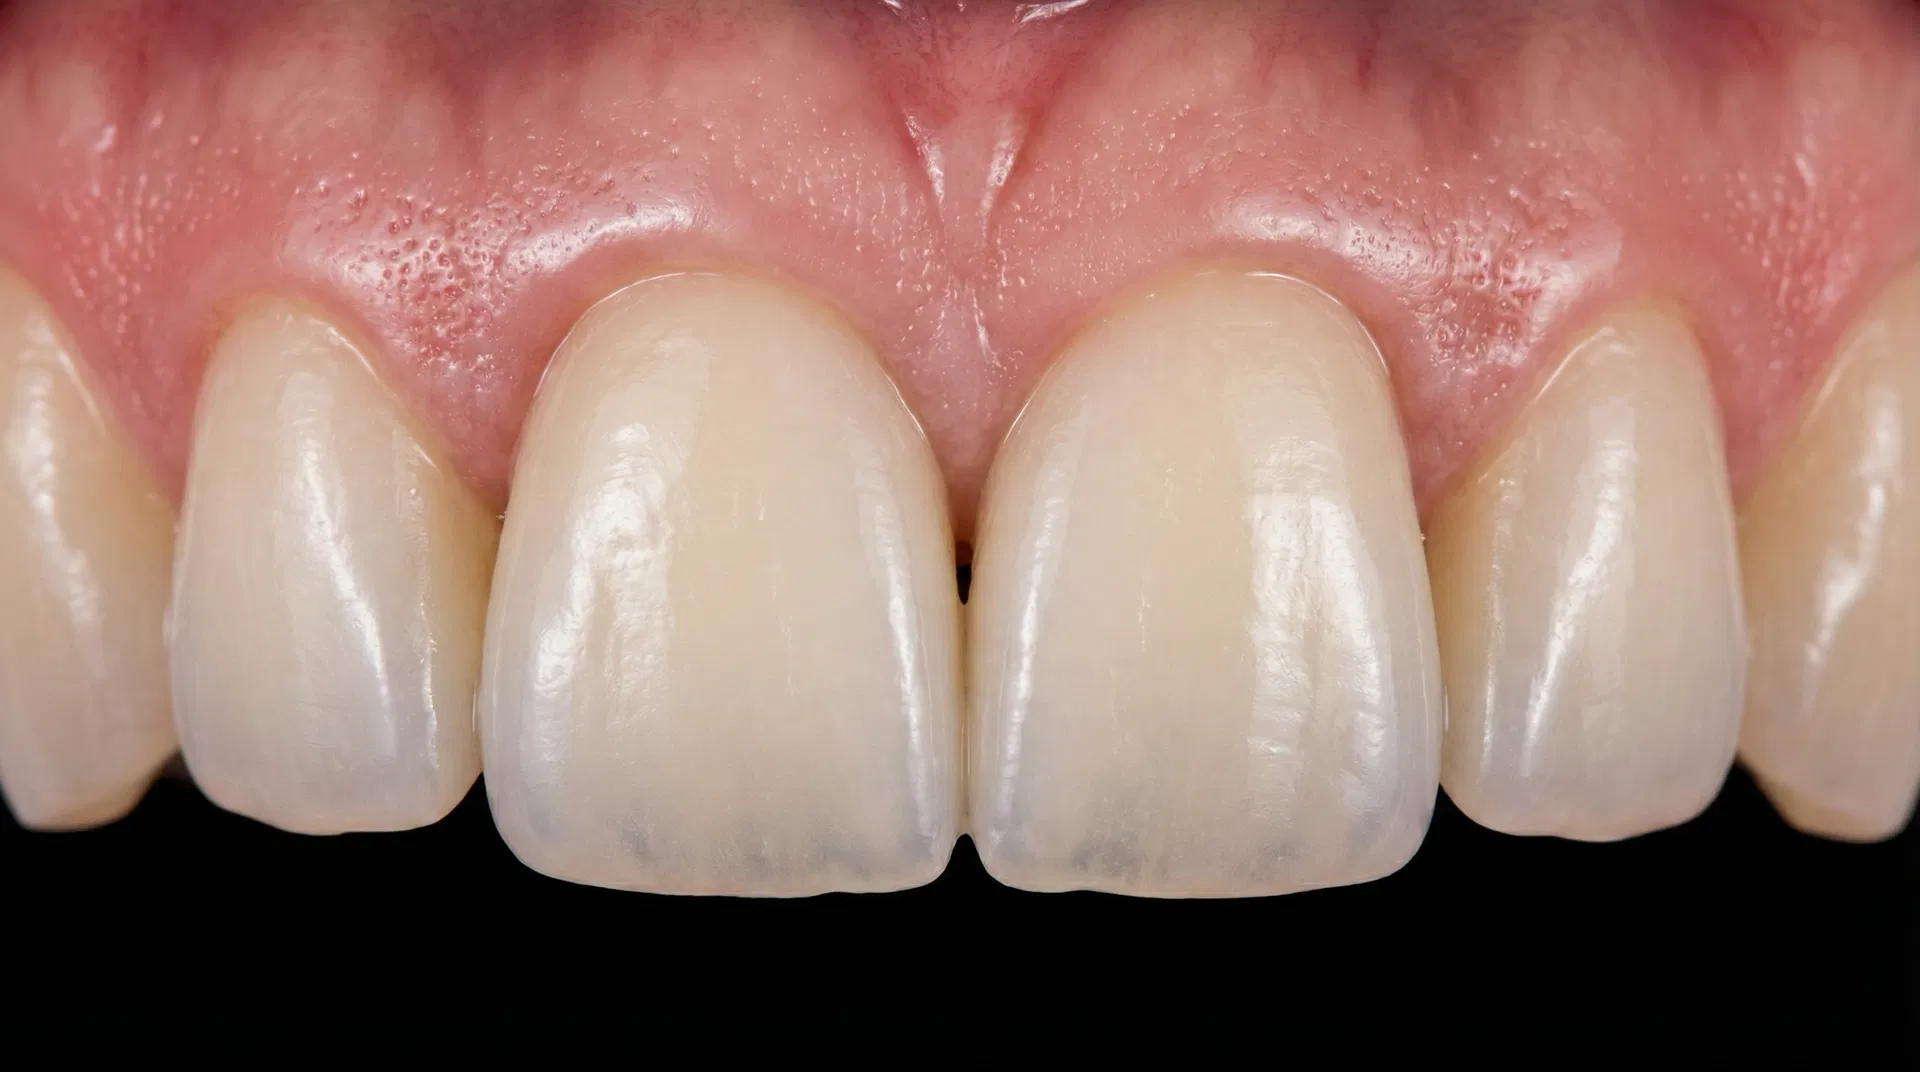

Before & After Transformations

See the life-changing results achieved by Dr. Nurein. Drag the slider to compare before and after treatment photos.

Note: Cases 2, 3, and 4 feature real patient results. Other cases are illustrative. Actual results may vary. Consult Dr. Nurein for a personalized assessment.

Single Tooth Implant

Missing upper front tooth replaced with a premium titanium implant and porcelain crown, restoring a natural, seamless smile.